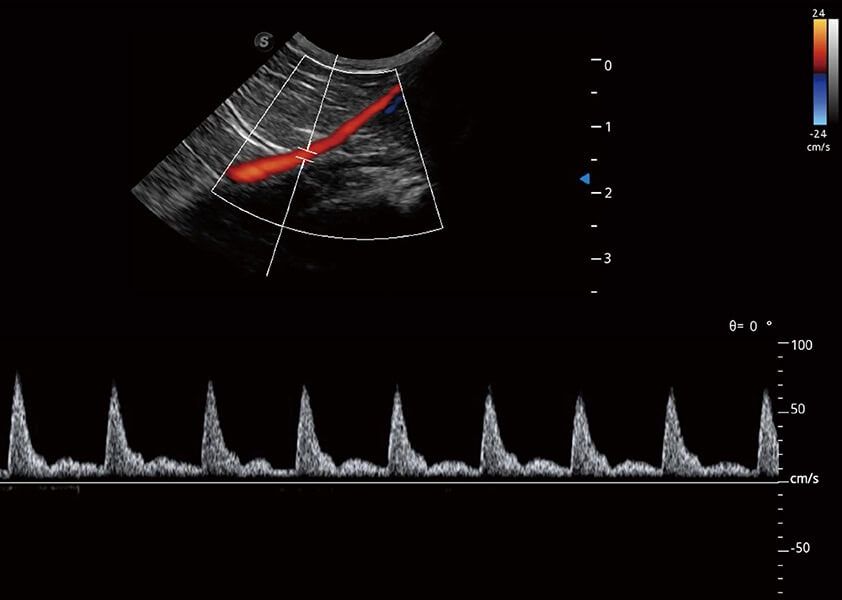

ProPet 60 作为一款高端台式动物超声设备,为动物医生的日常诊断提供了一系列贴合动物临床需求、解决临床实际问题的高级成像功能。凭借全系列高清探头,满足医生对腹部、心脏、生殖、浅表、肌骨等成像的所有需求,切实帮助您提升检查效率,提高诊断信心。

动物是人类最亲密的朋友和最值得信赖的伙伴。db真人体育官网也一直致力于探索动物专用的超声影像解决方案。 全新推出的ProPet系列,是db真人体育官网在动物超声影像智能化、专业化、精准化的一次跨越式革新。动物不能用言语来表述自己的不适,通过超声影像,ProPet系列搭建了动物医生与不同物种沟通的“桥梁”,为动物医生注入了“治愈之力”。